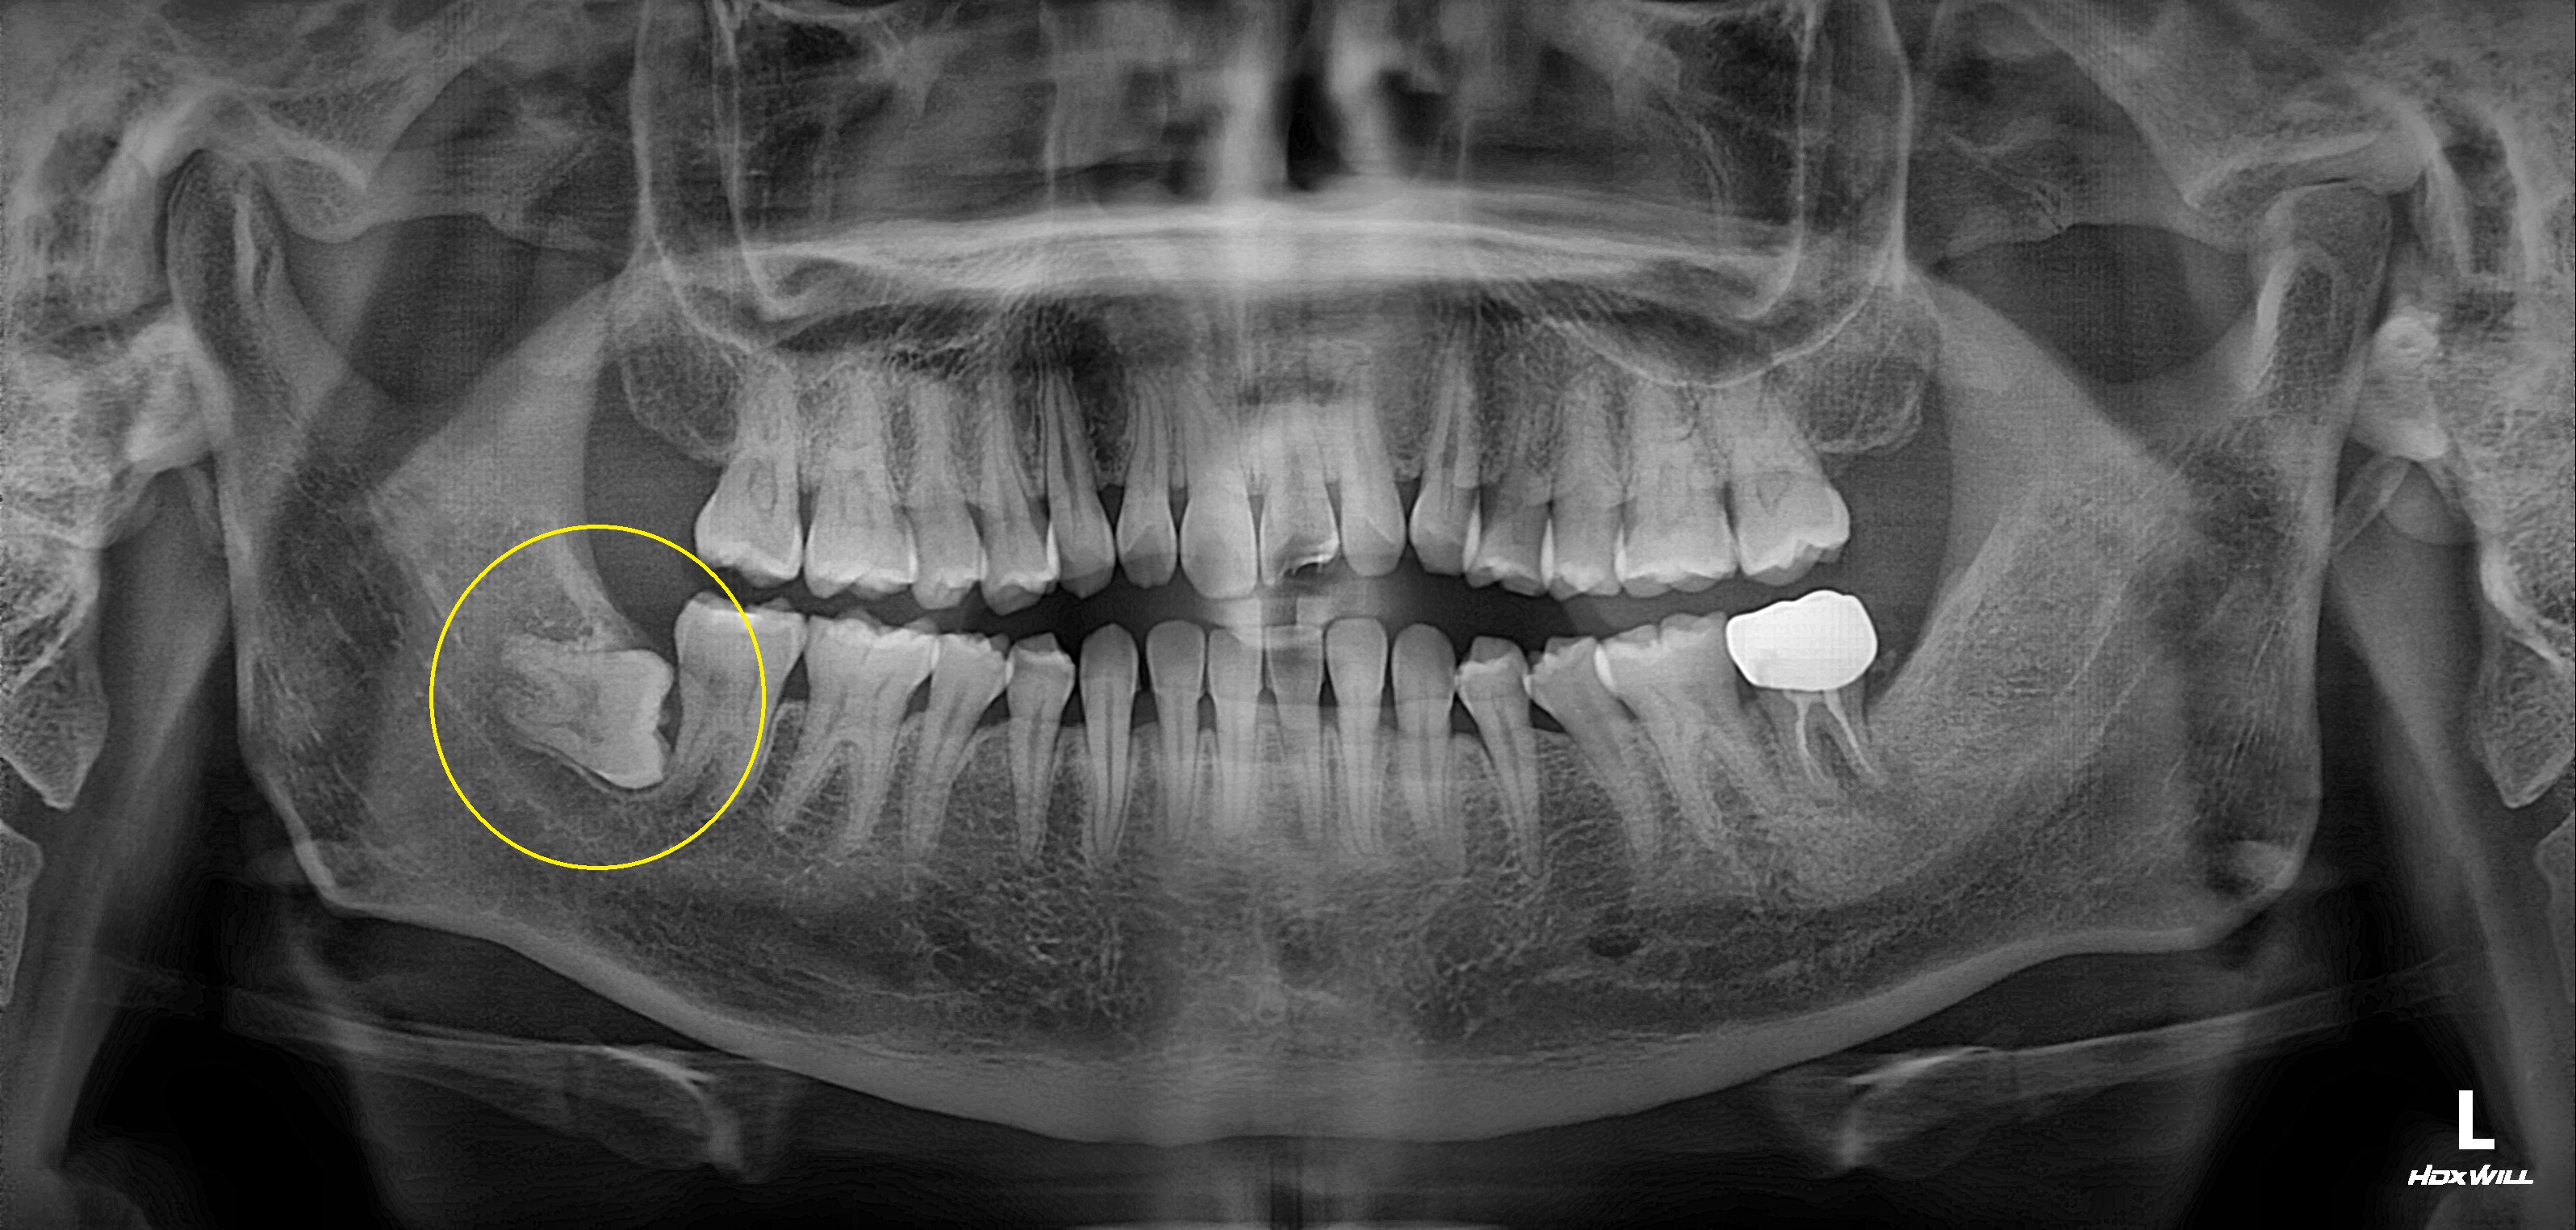

완전매복치 발치 사례

전후사진

수술 전

수술 후